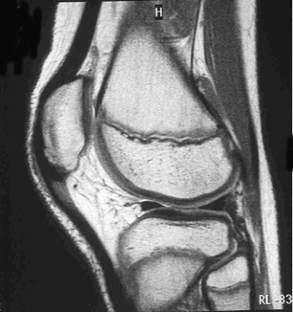

Fig. 4